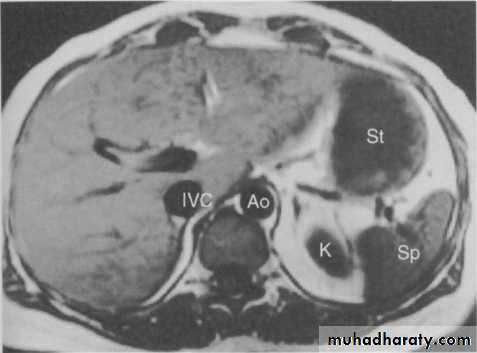

MRI of the liver

Magnetic resonance imaging is used as a problem-solving technique to give additional information to ultrasound and CT. Axial sections give images akin to CT but images can also be obtained in the coronal and sagittal planes. By using special sequences information can also be obtained on the arterial and venous circulation of the liver.Radionuclide liver imaging